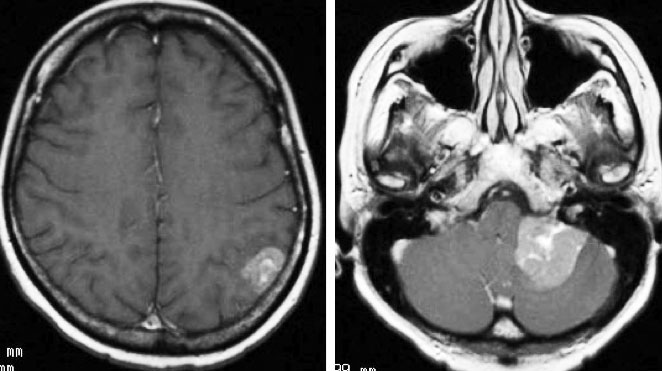

乳がんが脳転移した時の生存率 症状 治療法について解説する がん

乳がんが脳転移した時の生存率 症状 治療法について解説する がん